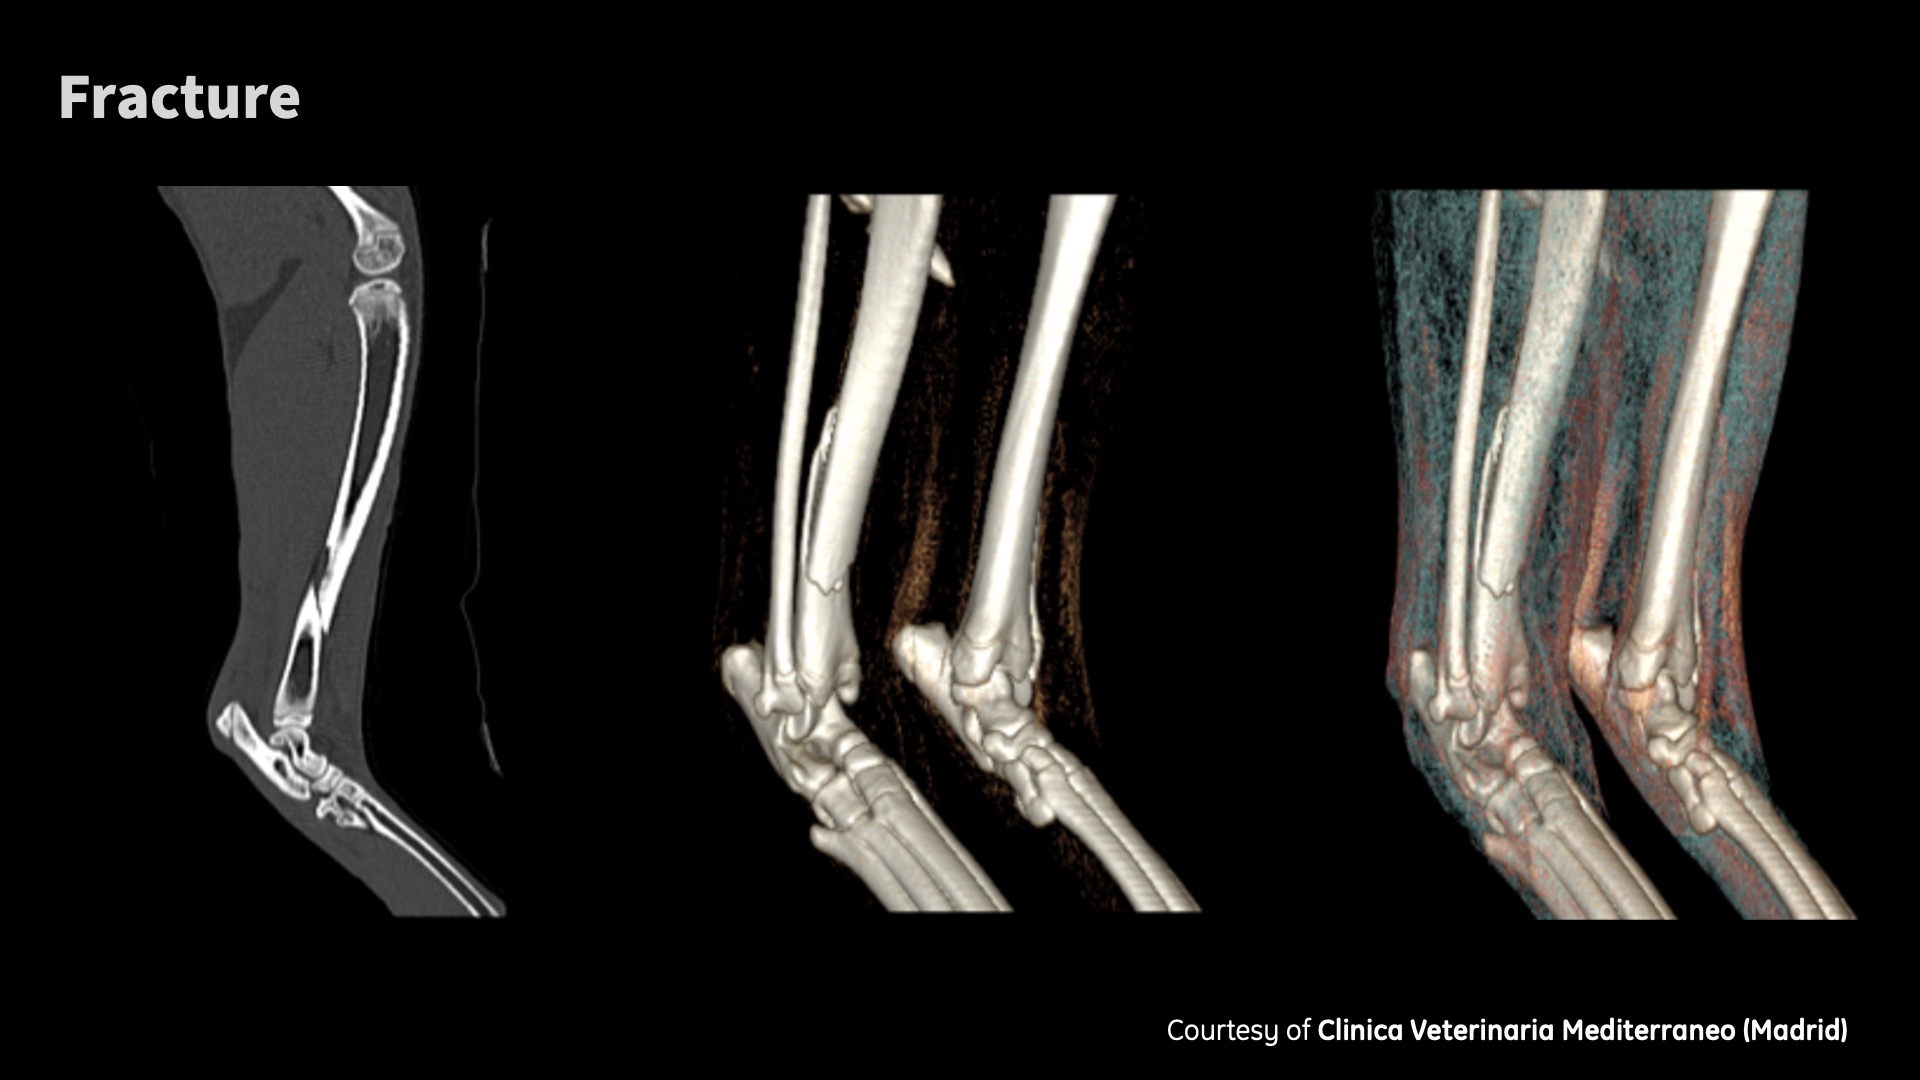

Clinical images

Don’t need to be an eagle to see the details